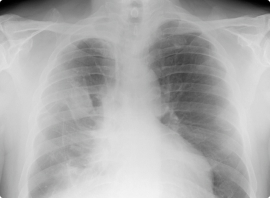

- Chest X-rays: With a chest radiograph or X-ray, doctors can see inside the chest and lungs. This is usually the first imaging test used to look for problems in the chest cavity.